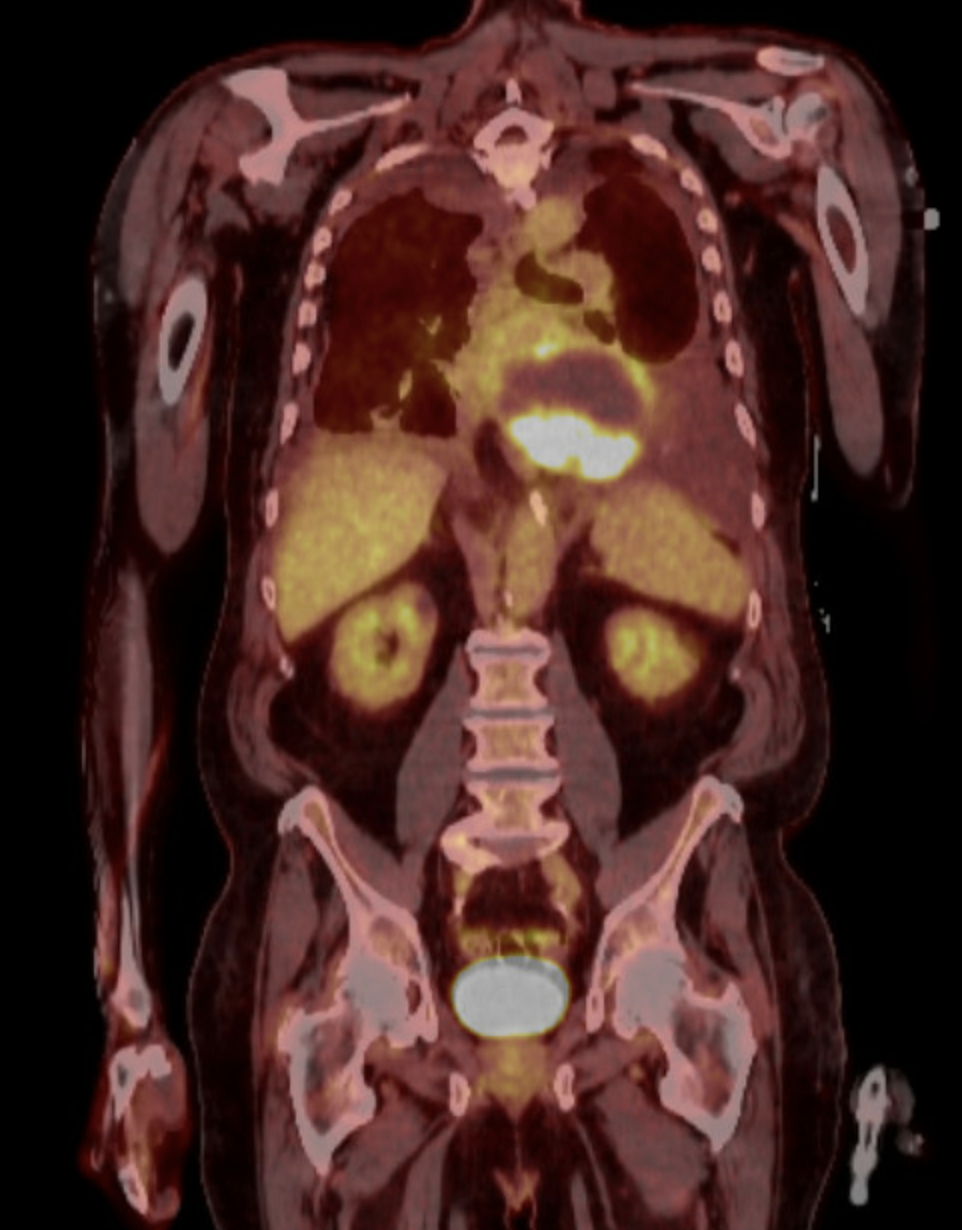

Case Description: An 81-year-old male with multiple comorbidities including hypertension, atrial fibrillation, bioprosthetic aortic valve replacement (2022), Crohn's disease, and HFmrEF presented with gastrointestinal symptoms. CT abdomen incidentally revealed a large pericardial mass (10×7 cm) compressing the left atrium and basal left ventricle, causing severe mitral stenosis (mean gradient 15 mmHg). Initial differential included mesothelioma and metastatic pulmonary sarcomatoid carcinoma. The patient underwent 10 sessions of palliative radiation. Post-radiation, he developed worsening nausea, vomiting, dysphagia, atrial fibrillation with RVR, and pleural effusions. Cardiac imaging (MRI [Figure 1] and PET [Figure 2]) confirmed the pericardial mass with compression effects and no distant metastases. Thoracentesis and supportive care provided temporary relief. Pericardial FNA pathology revealed a biphasic keratin-positive malignant neoplasm consistent with sarcomatoid carcinoma. Immunohistochemistry was positive for AE1/AE3, CK7, vimentin, and OSCAR. Negative markers ruled out mesothelioma, RCC, melanoma, and other sarcomas. Despite multidisciplinary input, the mass was inoperable. Planned AV nodal ablation and Micra pacemaker were deferred due to anesthetic risk. Inpatient chemotherapy (carboplatin + pemetrexed) was planned, but the patient decompensated before initiation.

Discussion: Sarcomatoid carcinoma of pericardial origin is undocumented. PET/CT imaging and immunohistochemistry were key to diagnosis. Tumor compression mimicked valvular and heart failure symptoms, complicating management. Despite early multidisciplinary care, prognosis was poor due to rapid clinical decline.